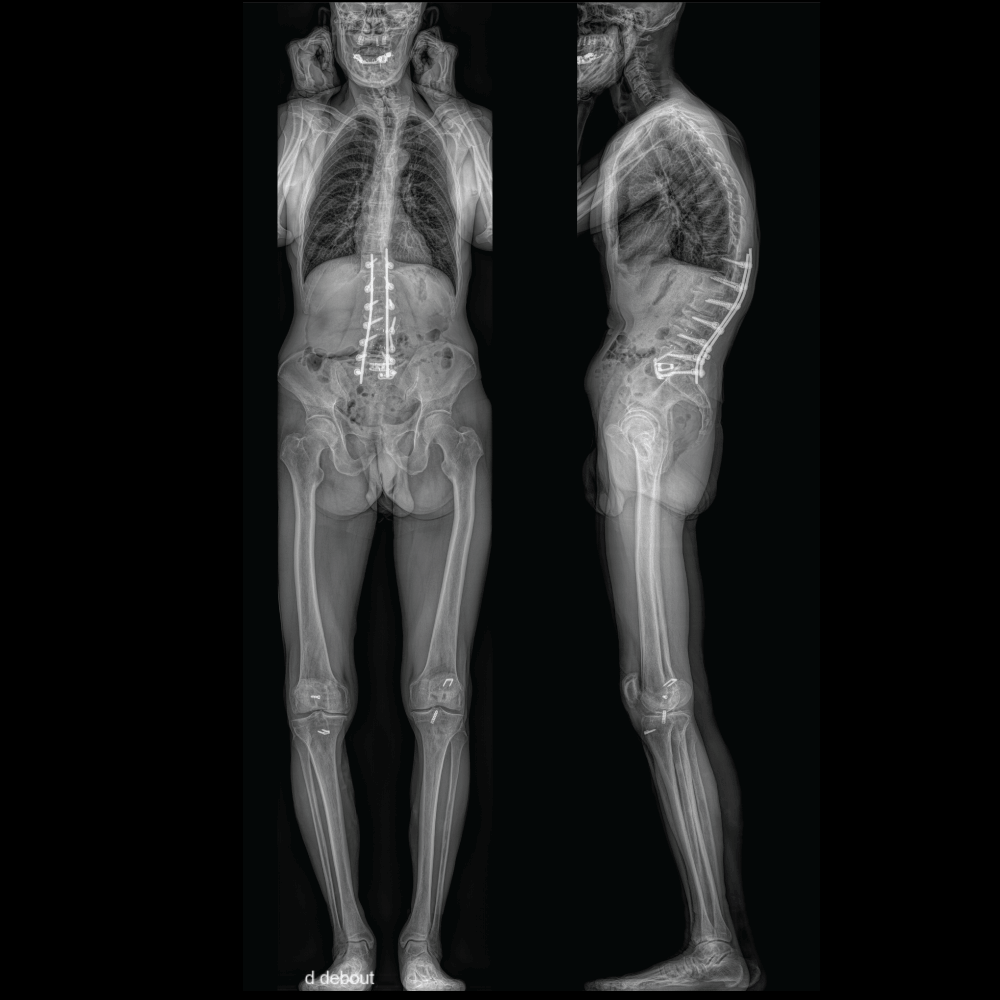

Post-Operative Patient

2. Full-Body Biplanar Imaging: By capturing a full-body image in a weight-bearing position, EOS provides a comprehensive view of the skeletal structure. This enables precise measurements of anatomical angles and dimensions, which are essential for accurate diagnosis and treatment planning in orthopedics.

3. High Resolution and Precision: The high-resolution images produced by EOS allow orthopedic physicians to examine details that may not be visible with conventional imaging methods. This helps in identifying the root cause of patients' conditions and in developing personalized treatment plans tailored to their specific needs.